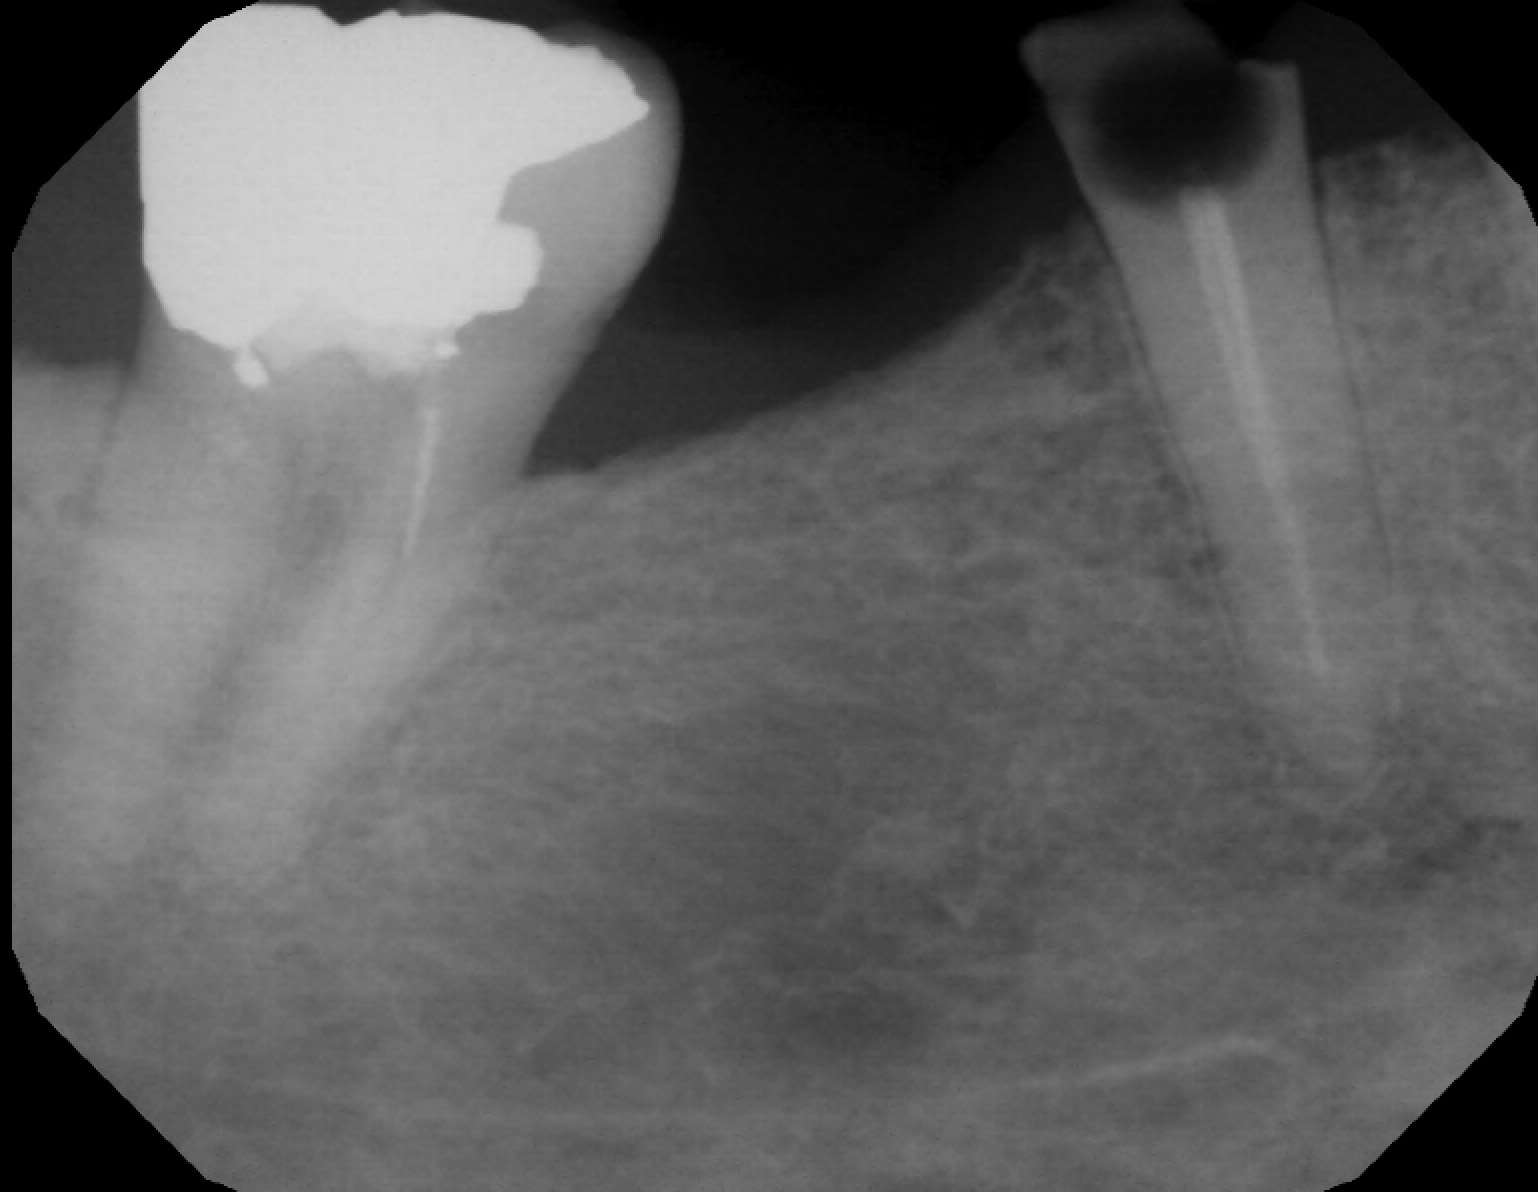

Note: 11 (US # 8) and 21 (US # 9) have caries into the pulp and peri apical lesions

• Residual roots: 45 (US # 29). Fractured: 44 (US # 28).

• Endodontic fillings: 15, 14, 44, 45, 47* (US # 4, 5, 28, 29 and 31*)

• Periapical lesion on 11 (US # 8) and 21 (US # 9): correlates with the clinical finding of eroded teeth down to the dentin (almost the dentino-pulp junction)

• Note : The root canal on tooth 47 (US # 31) was done in Algeria and seems to have been an attempt. There is a broken instrument in one of the canals.